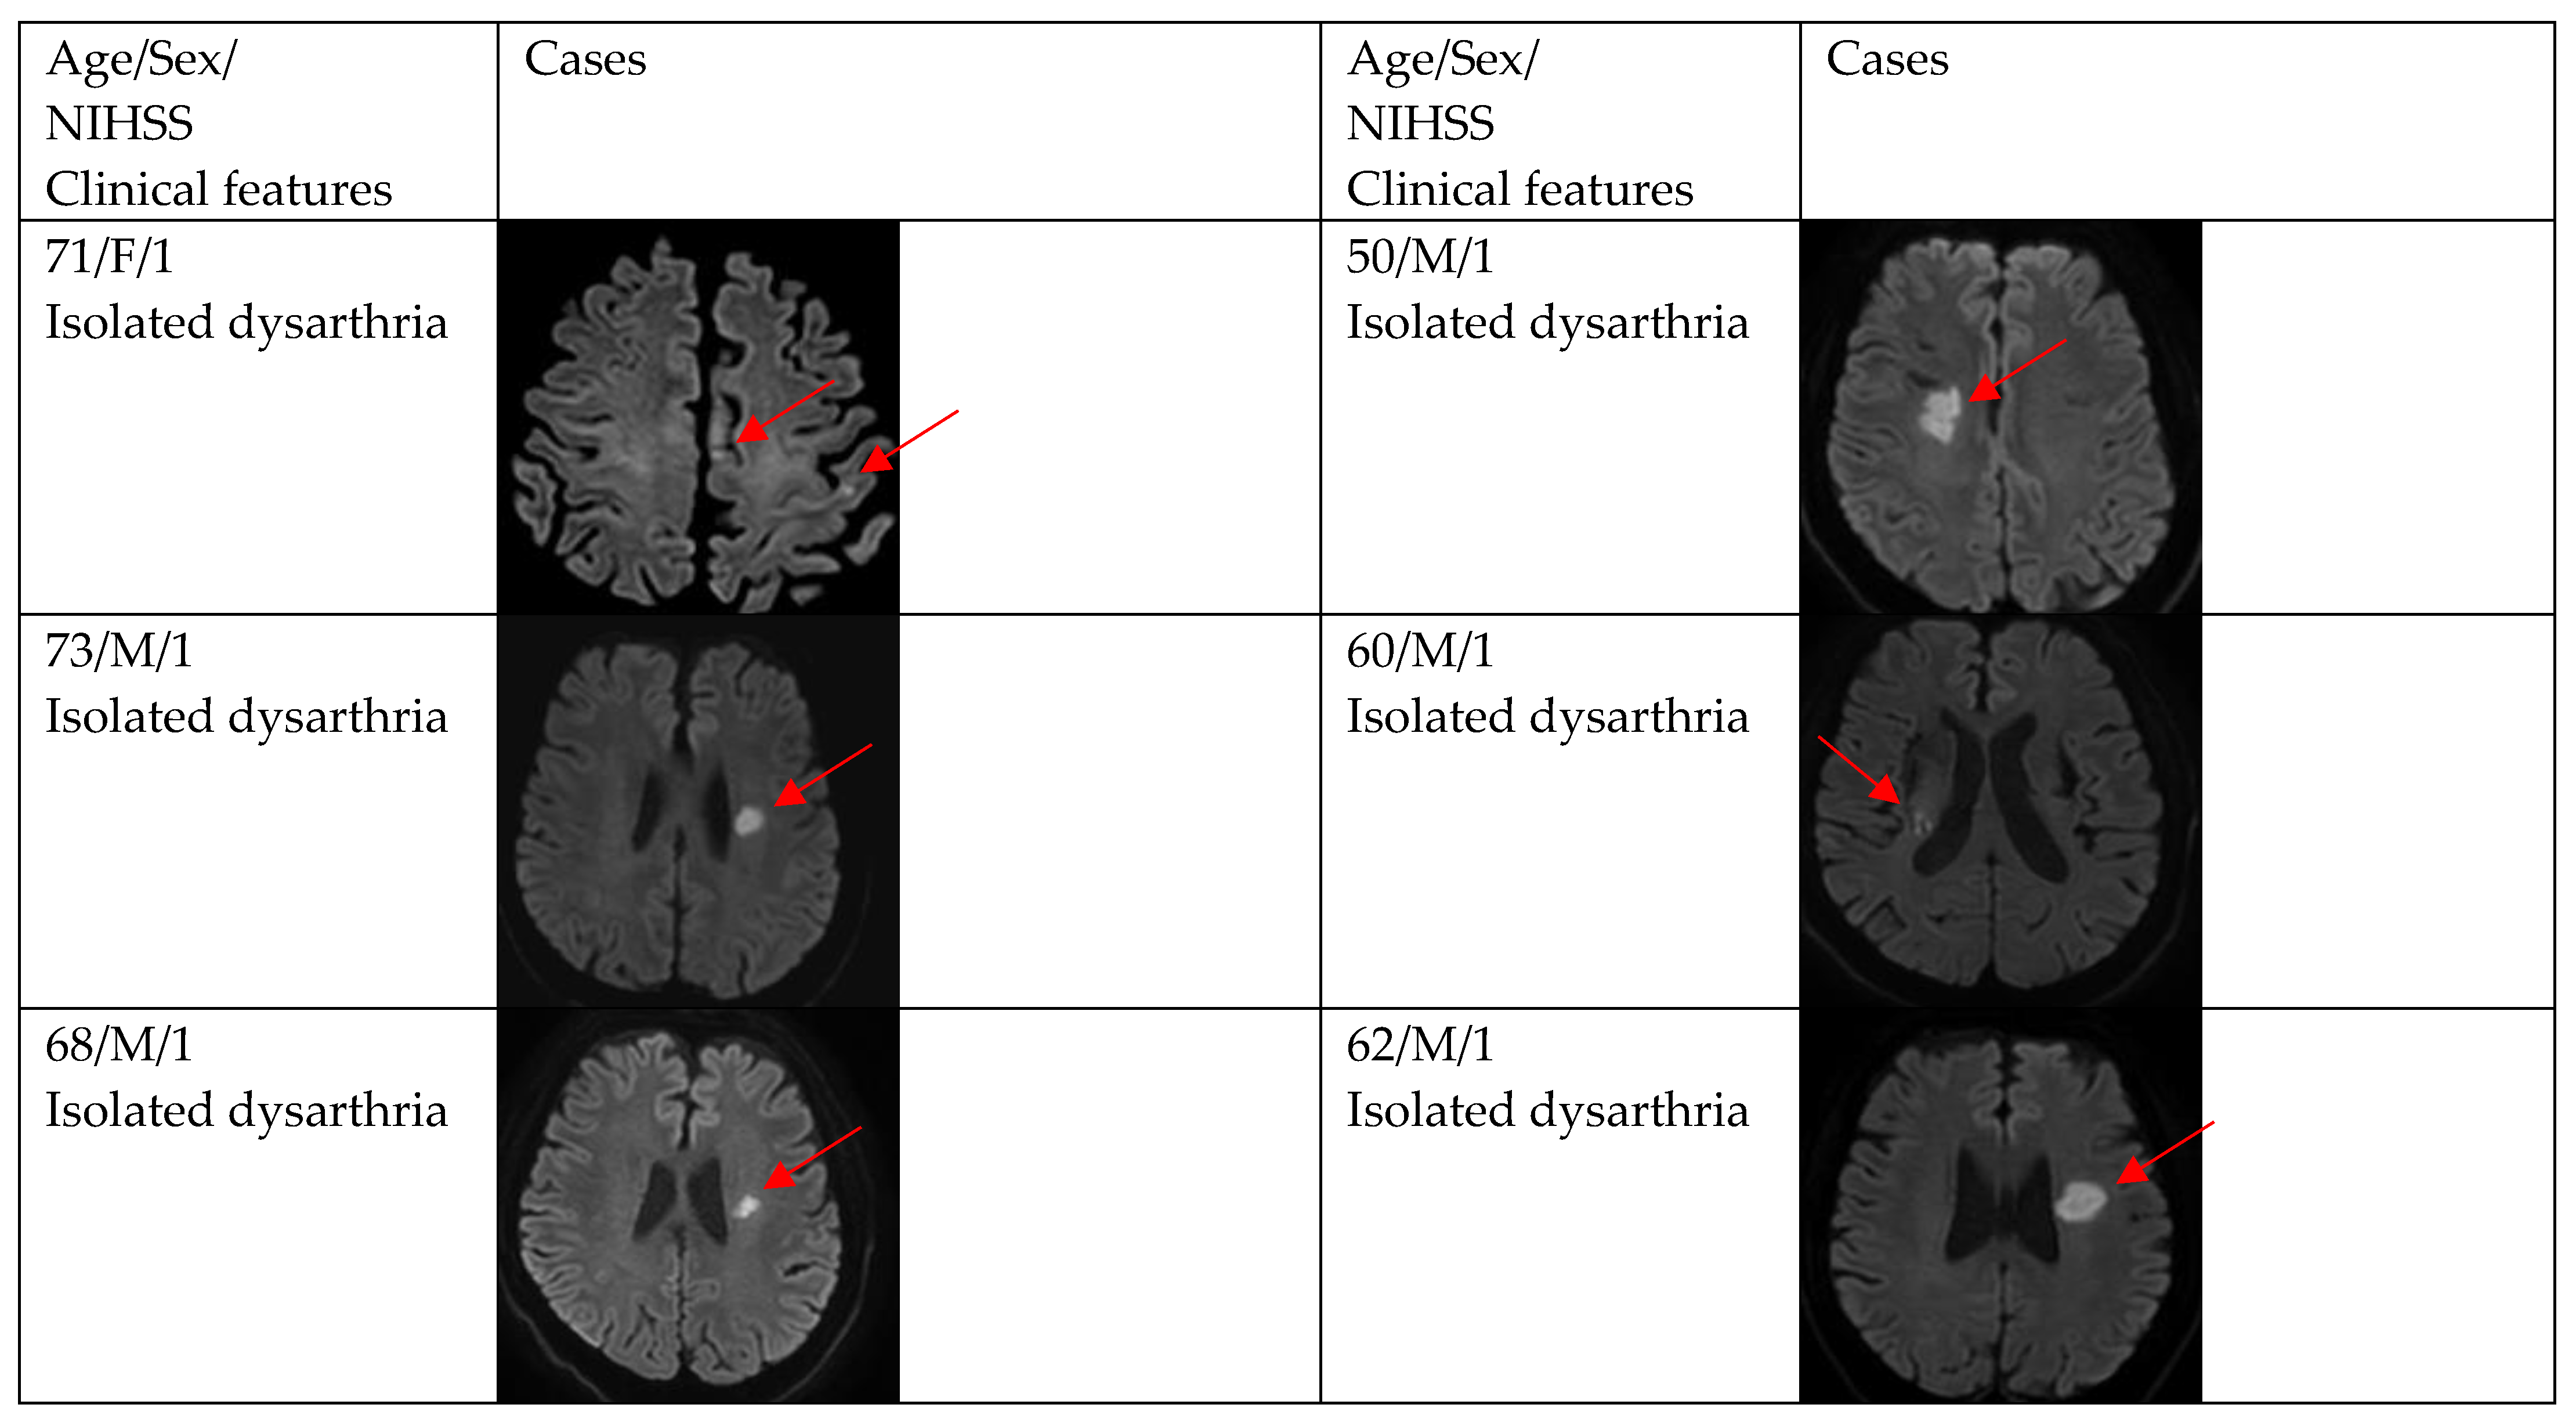

| DWI positivity | 12 (66.7) | 29 (87.9) | 0.154 |

| Single and small lesion | 10 (83.3) | 16 (55.2) | |

| Multiple or territorial lesions | 2 (16.7) | 13 (44.8) | |